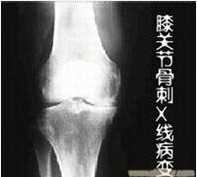

导读: 膝关节骨刺是人体自然老化现象,多由于膝关节在长时间反复使用下导致膝关节磨损、破坏,并促成骨头本身的修补、硬化与增生,多发于中老年人。那么,中老年人膝关节骨刺如何进行保养?下面一起来具体的了解一下。 中